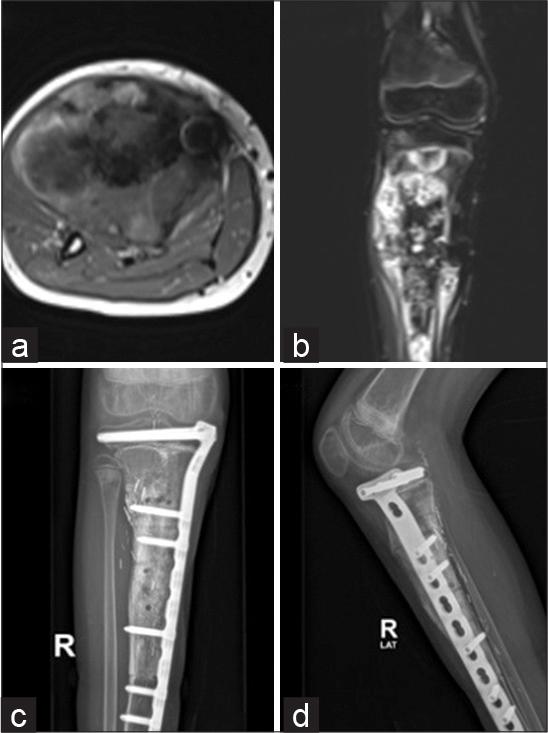

Figure 1:

Figure 2: